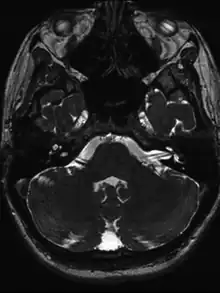

- Based on symptoms after ruling out other possible causes

- MRI